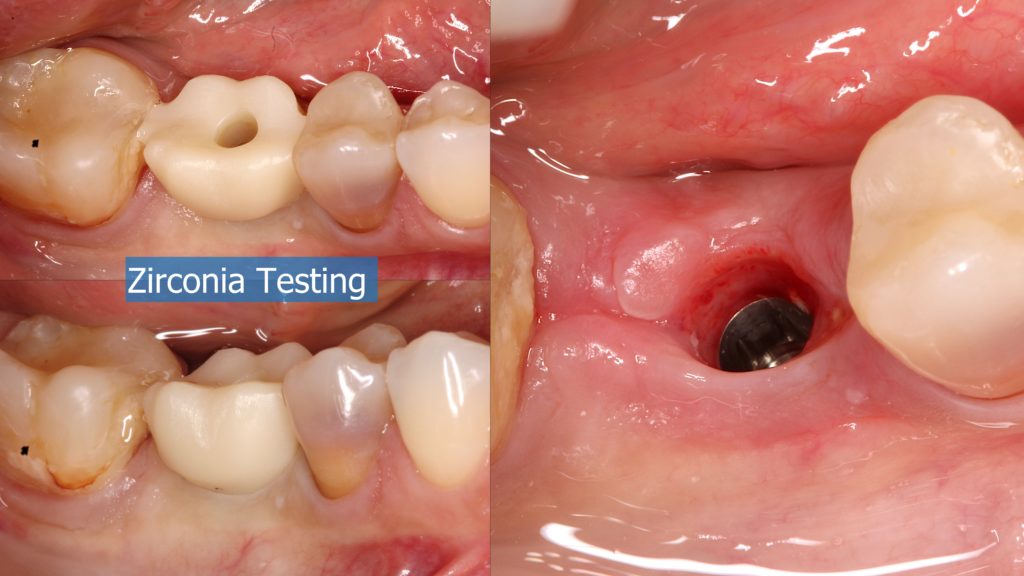

A healthy 36 year old woman comes to the clinic with pain and swelling in the area of the inferior left molars. In the intraoral observation, a vestibular fistula was identified, and the complementary exams confirmed a bone lesion caused by a root perforation (poorly executed false post) on the first lower left molar #36 (19). It was decided to do antibiotic therapy for a week and then the tooth extraction with immediate implant placement and bone graft. 4 months post-op the definitive zirconia/ceramic crown would be was made.